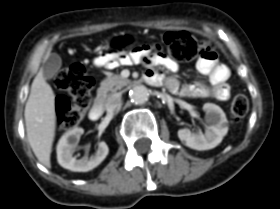

Refer to caption

(a) Input CT scan

(b) Annotations format 1

(c) Annotations format 2

Figure 2: Example illustrating the different annotation formats. Each subfigure shows the same axial section, with overlays depicting the annotations: (a) shows the axial CT section. (b) shows the annotations in format 1: parenchyma and kidney abnormalities as a single structure (yellow overlay). (c) shows the annotations in format 2: parenchyma (yellow overlay) and kidney abnormalities (red overlay) as different structures. All images have a window center of 60 HU and a window width of 360 HU.

This study utilized two annotation formats, format 1 and format 2, to store the annotations. Format 1 considers the kidney parenchyma and kidney abnormalities as a single class (see Figure 2(b)) while format 2 separates them into two classes (see Figure 2(c)).